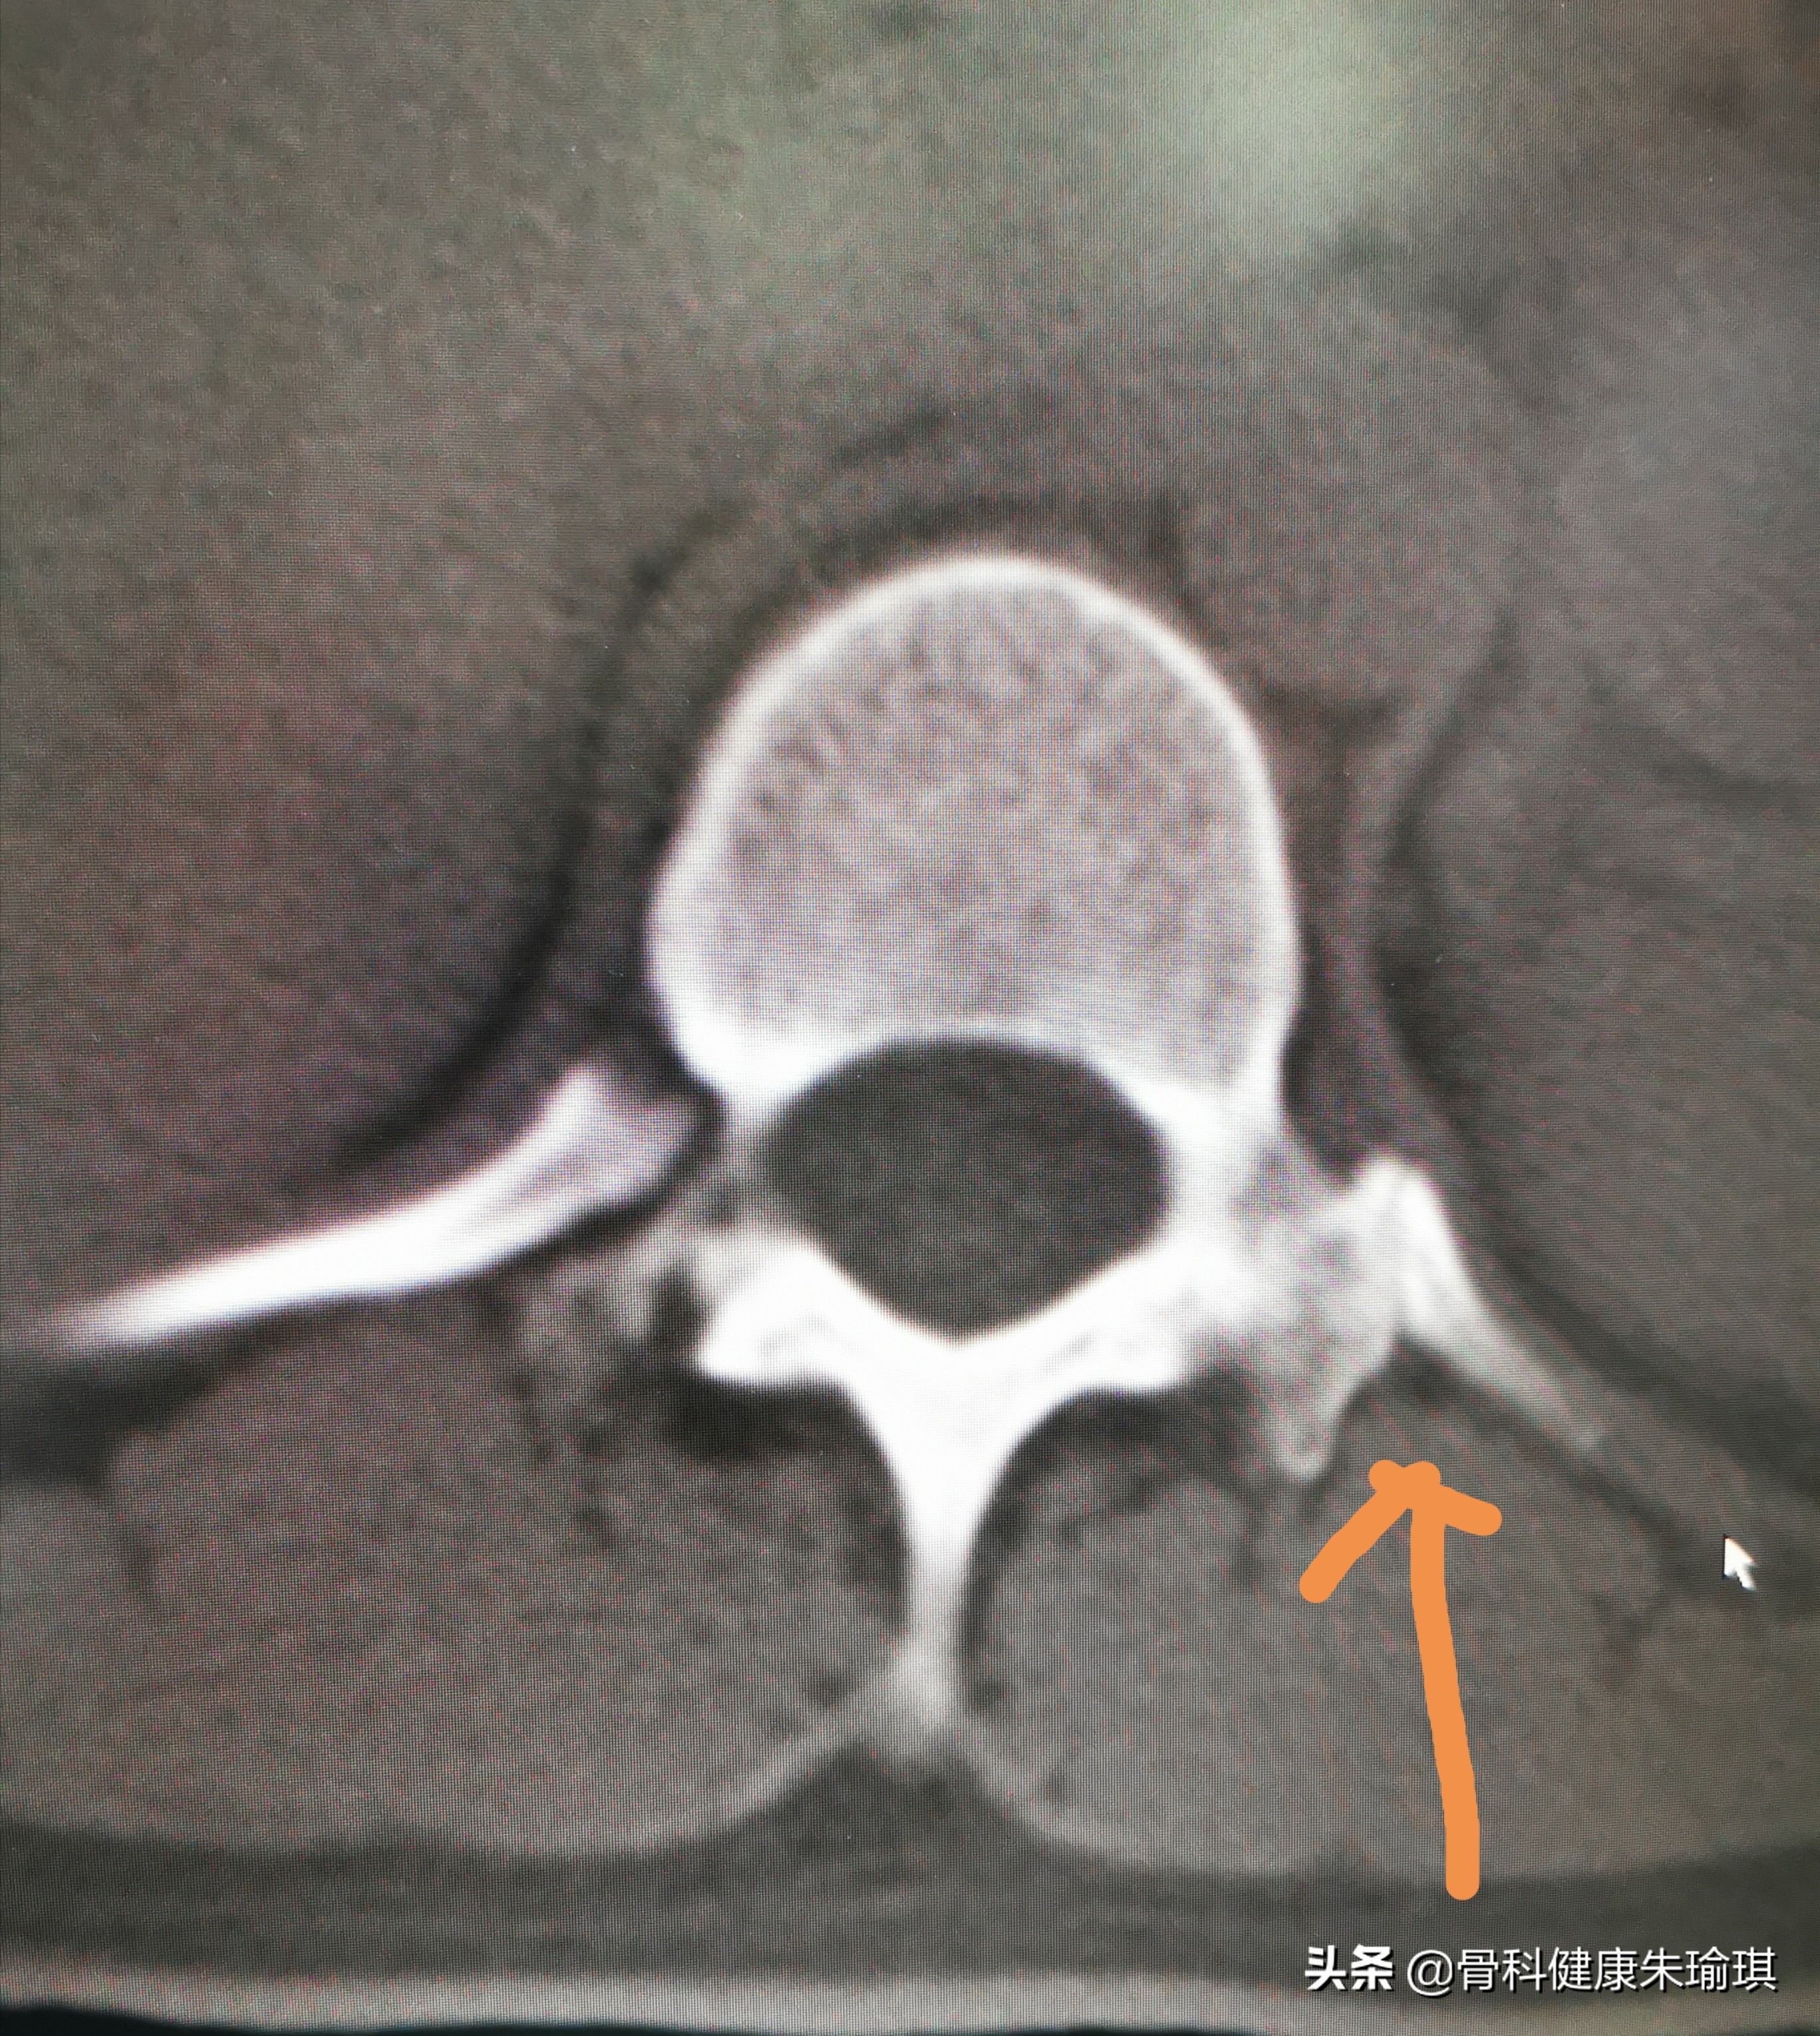

那么,我们再回到临床检查:右侧腰肌稍微有一些僵硬、痉挛,广泛压痛,但在胸12、腰1、腰2这几个节段的棘突旁的两侧并没有明显的深压痛。只是在腰45附近的右侧有轻微的深压痛,那么从临床检查的结果来看也不支持这个地方有骨折,为了明确诊断,也进一步证实我的判断,在征求患者同意后,又给病人做了CT的扫描检查,那么结果就是下面这张图,诊断就很明确了,真的没有骨折发生!。也进一步验证了这就是第12胸椎,这只是左侧的肋椎关节,并非是横突的骨折。

左侧第12肋头关节